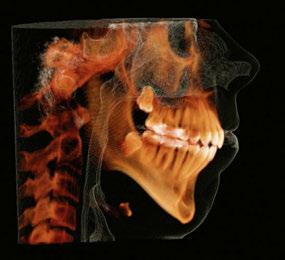

Patient background and initial presentation

Grant presented to my office as a healthy, well-adjusted teenager with ongoing concerns about his pronounced overjet which was causing difficulty with chewing, speech, and esthetics. He was a severe Class II vertical skeletal pattern, with vertical maxillary excess and a steep mandibular plane angle. His maxillary incisors were excessively proclined, resulting in severely increased overjet and mentalis strain. A maxillary transverse deficiency with a tapered arch form was also noted. Both arches

Figure 1: Initial images

were crowded, and the mandibular anterior tissue was thin with inadequate oral hygiene likely exacerbated by increased mouth breathing from the lip incompetence at rest.

Due to his obtuse nasolabial angle, tapered arch form, and mild crowding, upper premolar extraction to camouflage the Class II malocclusion was not considered. I did seek to reduce the lower third of his face as well as reduce the vertical excess of his maxilla and felt that posterior intrusion of the maxillary teeth was indicated to allow autorotation of the mandible and assist in reduction of the overbite and overjet.

Treatment plan and progress

On April 22, 2022, I placed the custom MARPE using 4 palatal TADs. I placed the TADs myself during a routine office visit, with local anesthesia performed prior to the procedure at his general dentist’s office. The appliance was co-designed and printed by Partners Dental Studio in Minneapolis, Minnesota. The length of the TADs was determined by CBCT analysis to provide bicortical engagement, and the lumens of the appliance were printed to precisely guide the TADs to their desired location. We began turning the expander on the day of delivery.

A diastema was visible after the first few days of turning, and I discontinued expansion after approximately 6 mm of expansion had been achieved.